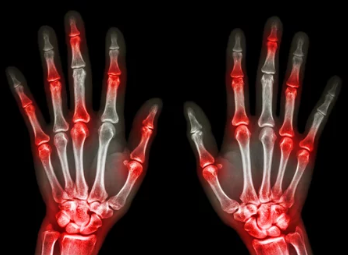

- 관절 부위의 발적, 부종, 열감: 엄지발가락 외에도 발목, 무릎, 손목, 팔꿈치 등 다른 관절 부위에도 통풍 발작이 발생할 수 있습니다. 관절 부위가 빨갛게 붓고 뜨거워지며, 심한 통증이 동반됩니다.